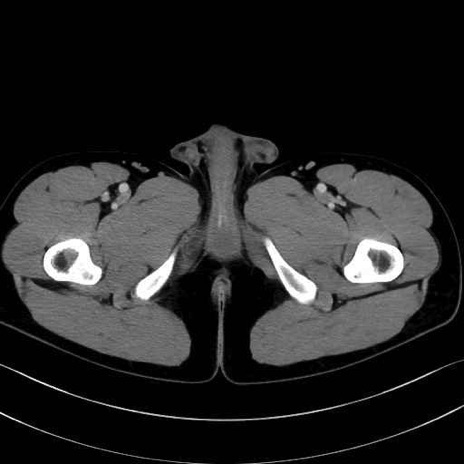

内閉鎖筋 (Obturator internus)

大腿方形筋 (Quadratus femoris)